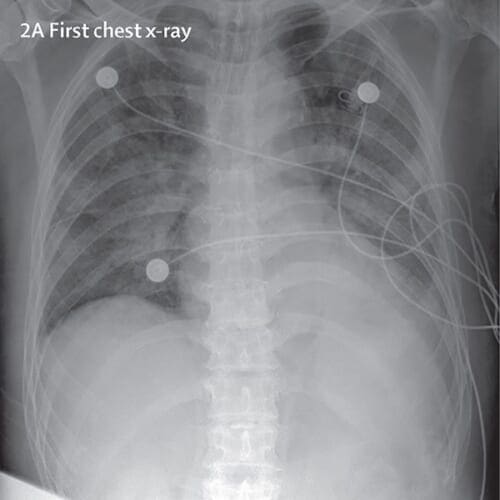

For the purposes of this tutorial, I thought to explore X-ray images as doctors frequently use X-rays and CT scans to diagnose pneumonia, lung inflammation, abscesses, and/or enlarged lymph nodes.

Since COVID-19 attacks the epithelial cells that line our respiratory tract, we can use X-rays to analyze the health of a patient’s lungs.

And given that nearly all hospitals have X-ray imaging machines, it could be possible to use X-rays to test for COVID-19 without the dedicated test kits.

A drawback is that X-ray analysis requires a radiology expert and takes significant time — which is precious when people are sick around the world. Therefore developing an automated analysis system is required to save medical professionals valuable time.

In total, that left me with 25 X-ray images of positive COVID-19 cases (Figure 2, left).

To do so, I used Kaggle’s Chest X-Ray Images (Pneumonia) dataset and sampled 25 X-ray images from healthy patients (Figure 2, right). There are a number of problems with Kaggle’s Chest X-Ray dataset, namely noisy/incorrect labels, but it served as a good enough starting point for this proof of concept COVID-19 detector.

After gathering my dataset, I was left with 50 total images, equally split with 25 images of COVID-19 positive X-rays and 25 images of healthy patient X-rays.